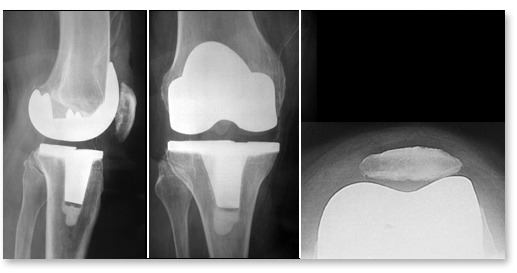

L’opération dure en moyenne 1h30. Le chirurgien ne remplace pas tout le genou. Il retire uniquement les surfaces de cartilage abîmées et les remplace par des implants (les composants de la prothèse) en métal et en polyéthylène (un plastique très résistant) qui restaurent un glissement fluide et indolore. Les ligaments principaux sont généralement conservés.